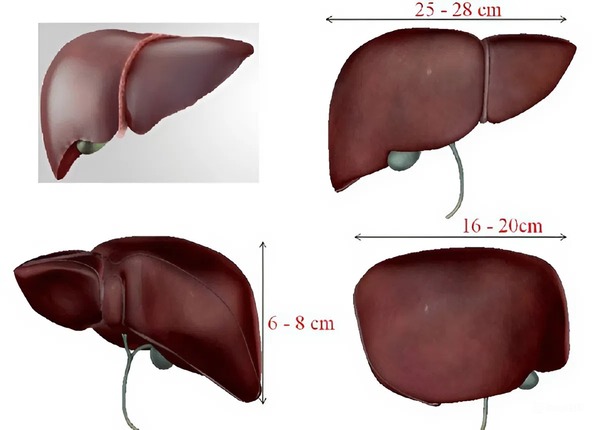

Kích thước gan bình thường là bao nhiêu?

Gan là một cơ quan nội tạng lớn với nhiều chức năng quan trọng, và những thay đổi về kích thước gan có thể là dấu hiệu sớm của nhiều bệnh lý nghiêm trọng. Trong các lần khám sức khỏe định kỳ hoặc khi thực hiện siêu âm, việc đo lường kích thước gan khi ...